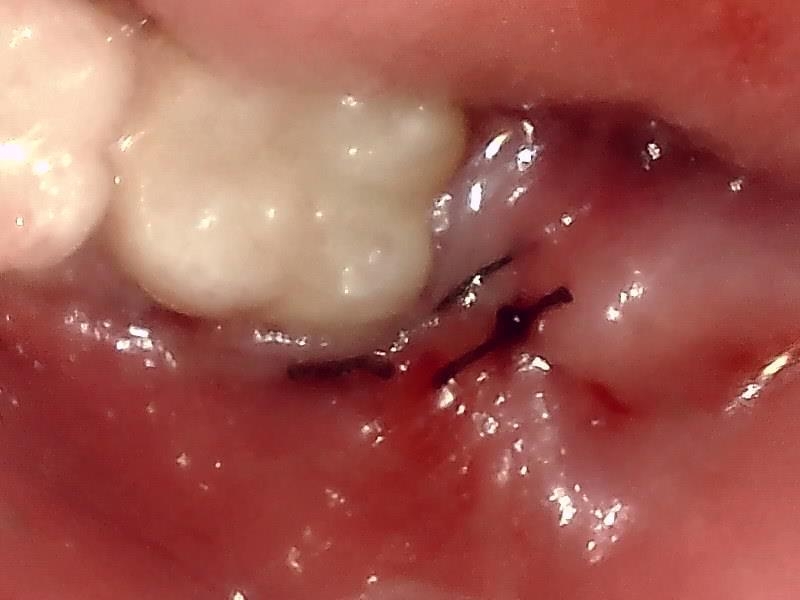

(左下)抜歯窩

切開して歯肉剝離する。

歯牙分割して抜歯する。

縫合